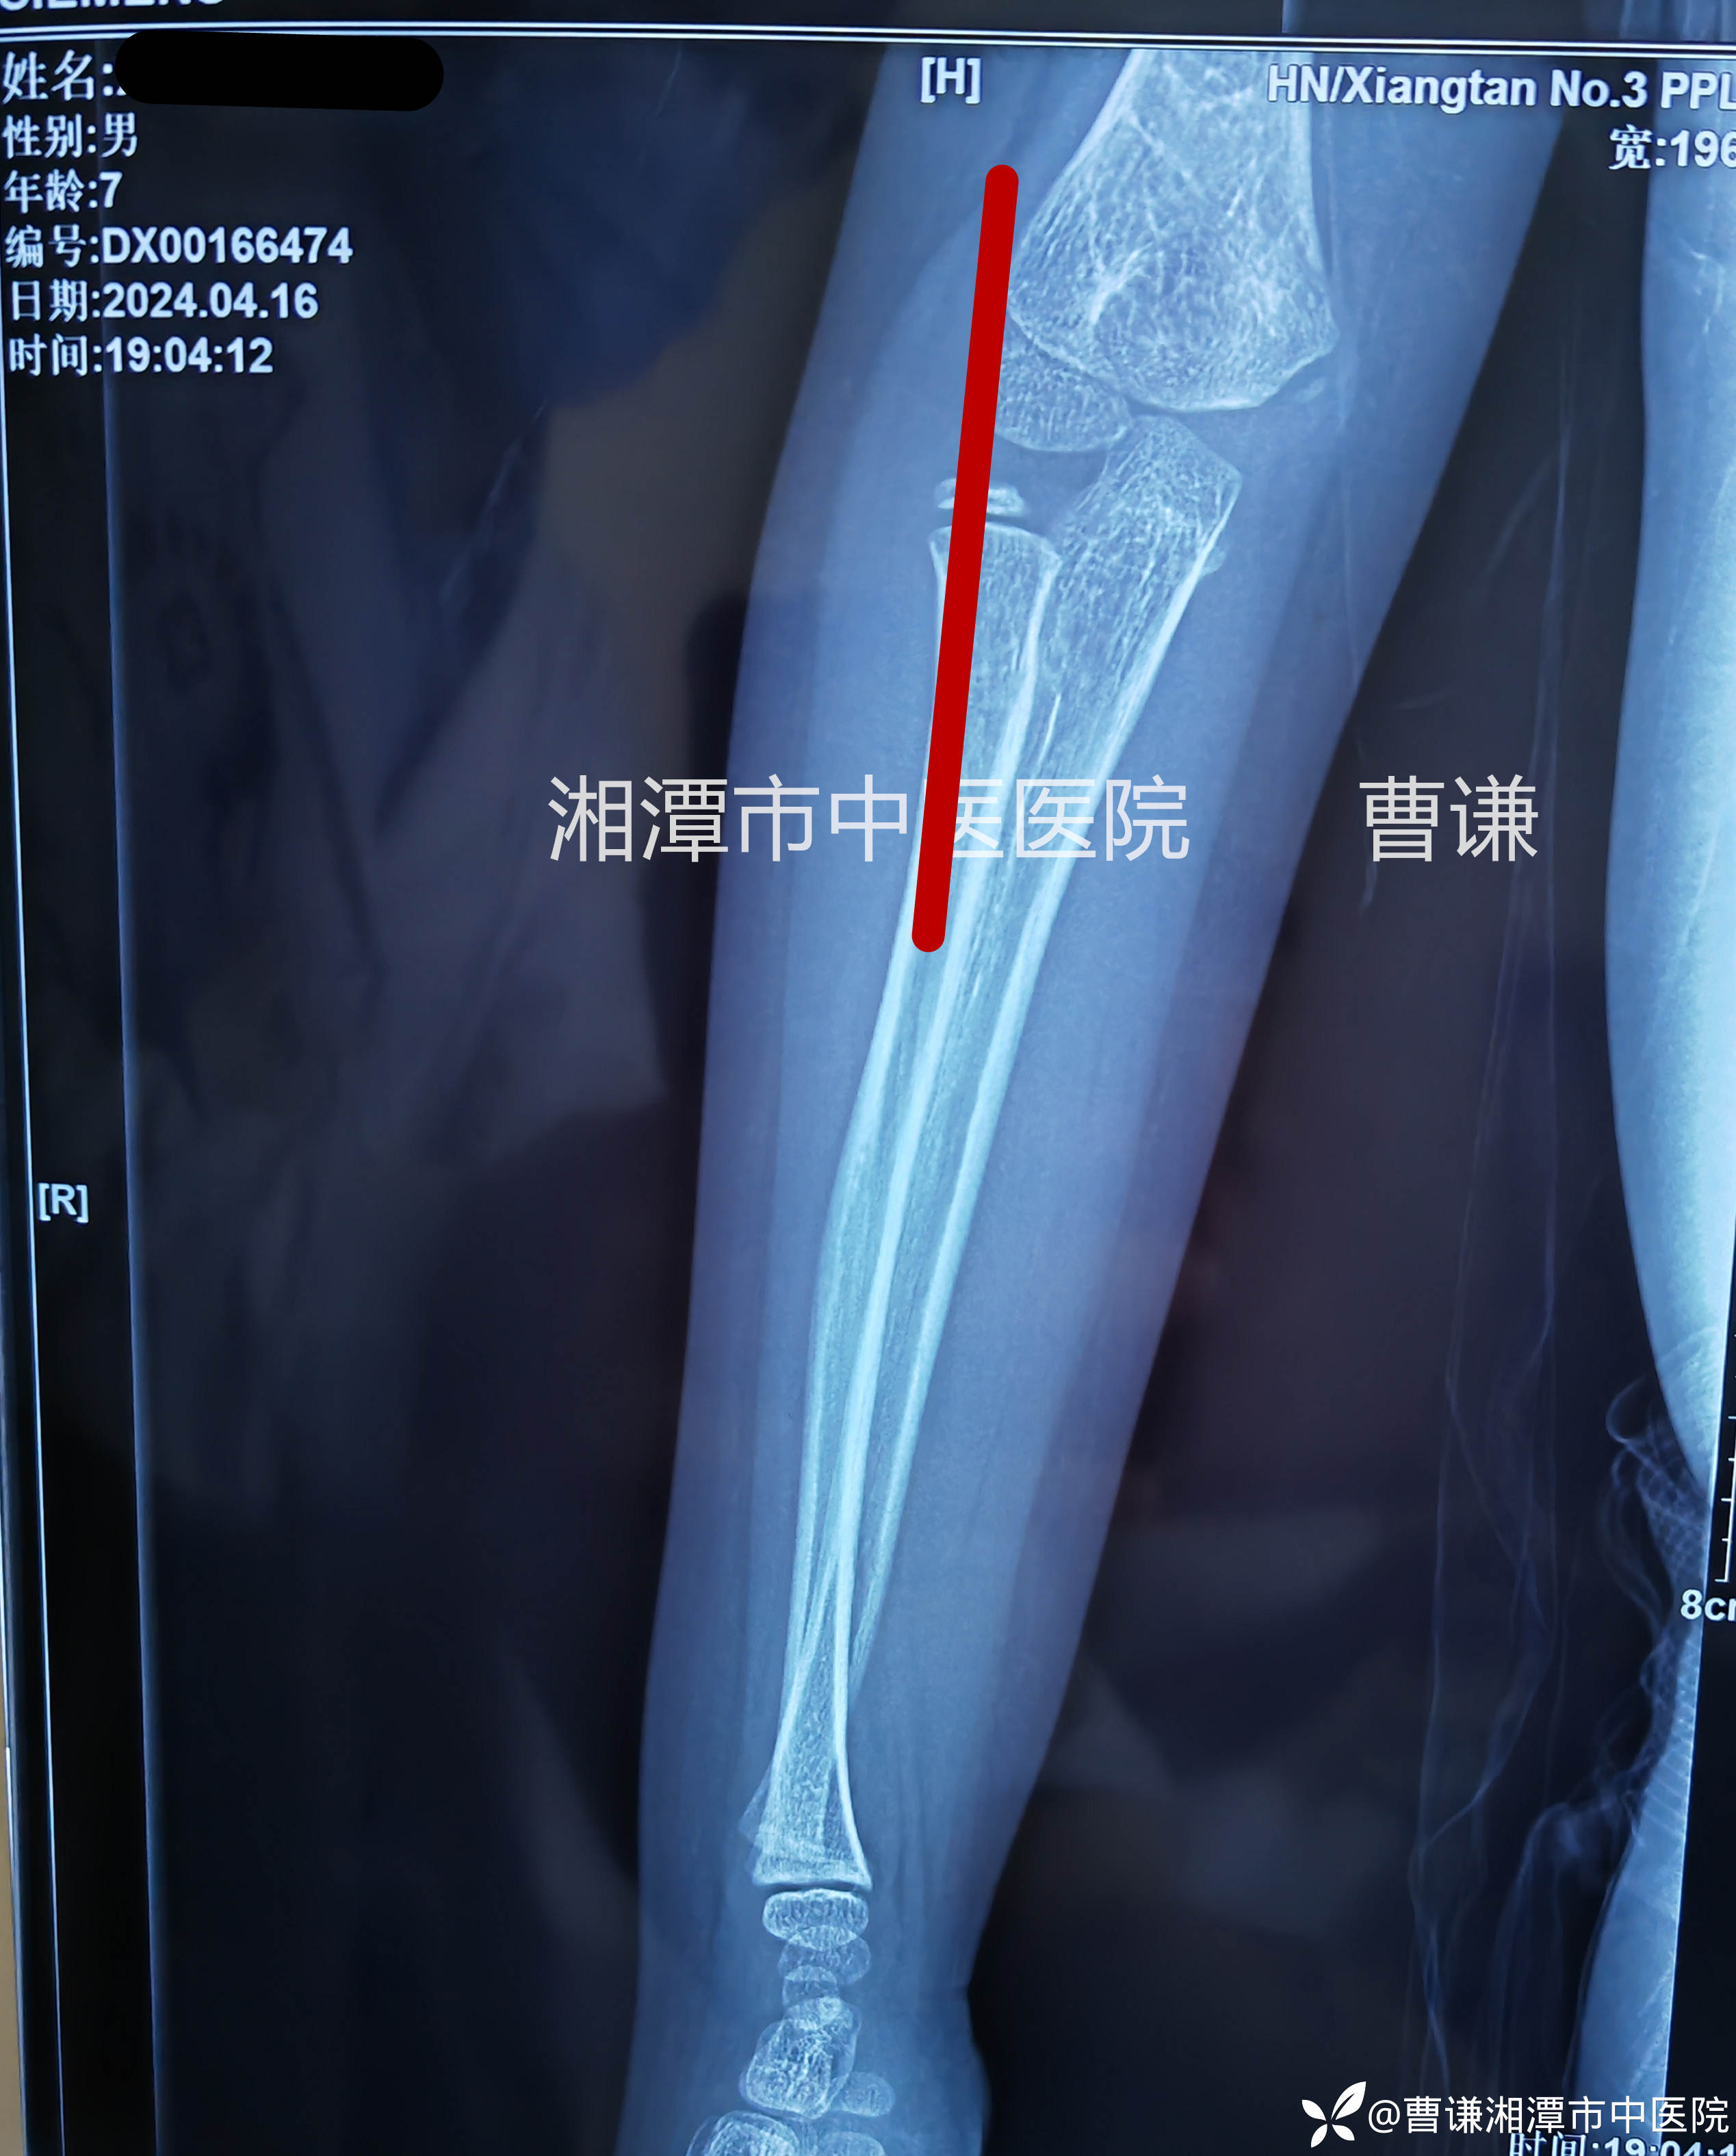

小医生实在没看出啥,还好并不傻,他沿着主任的目光所及之处终于发现肱桡关节匹配不良。再仔细体查患肢肘关节周围压痛,以桡骨头处及尺骨鹰嘴处明显。看来是个隐匿性的孟氏骨折啊!

固定完成拍片复查示肱桡关节匹配良好。